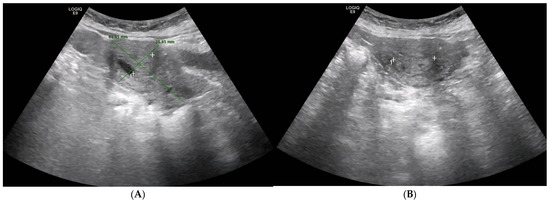

2. Case Presentation